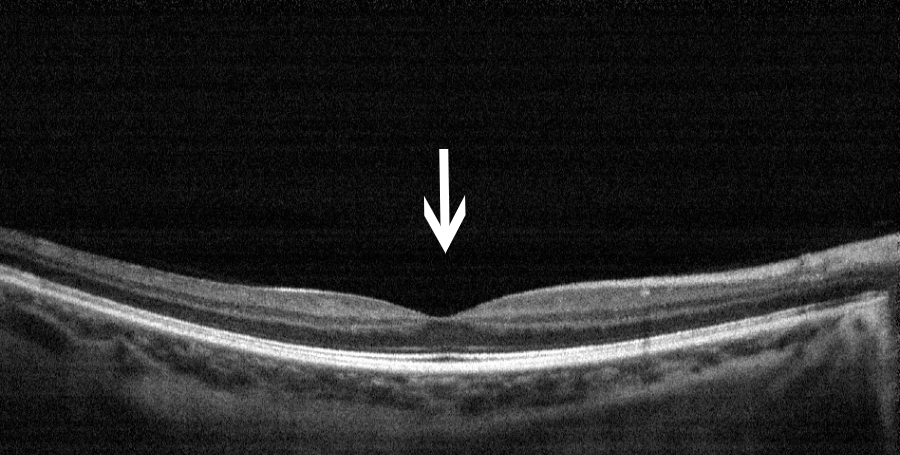

秦先生激光损伤后一周(左图)与两周(右图)的黄斑中心凹对比图,可见